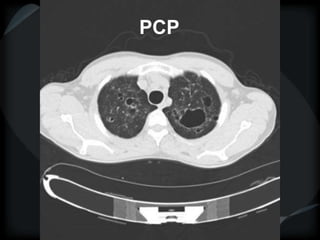

PCP

LIP

 Ground glass centrilobular nodules

 Diffuse ground glass

 Thin walled cysts

 PCP, papilomatosis, Birt-Hogg-Dube disease